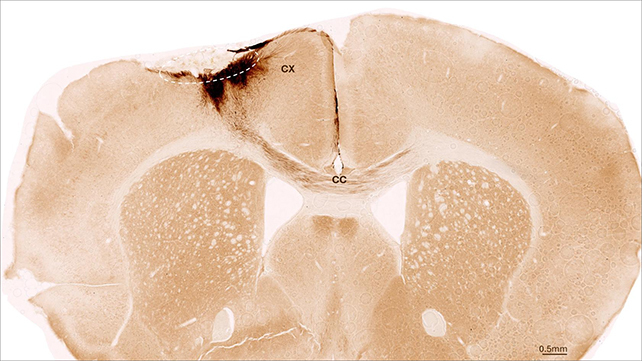

თაგვის ტვინის სურათი, რომელზეც ასახულია ინსულტის არე (წყვეტილი წრე) და გადანერგილი ადამიანის ღეროვანი უჯრედების პროექციები (მუქი ყავისფერი).

ფოტო: UZH